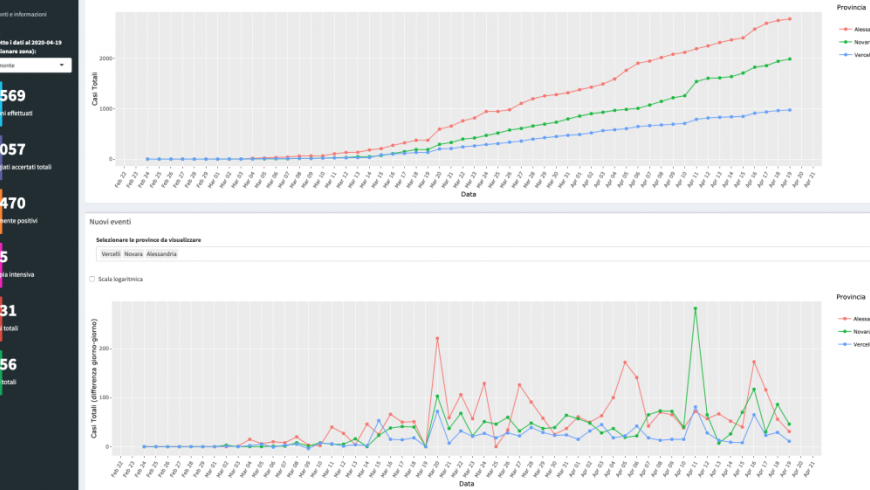

Ricercatori UPO collaborano al progetto di monitoraggio promosso dall'Università degli Studi di Padova

Argomento Scienza e Ricerca

Data di pubblicazione 19 Aprile 2020